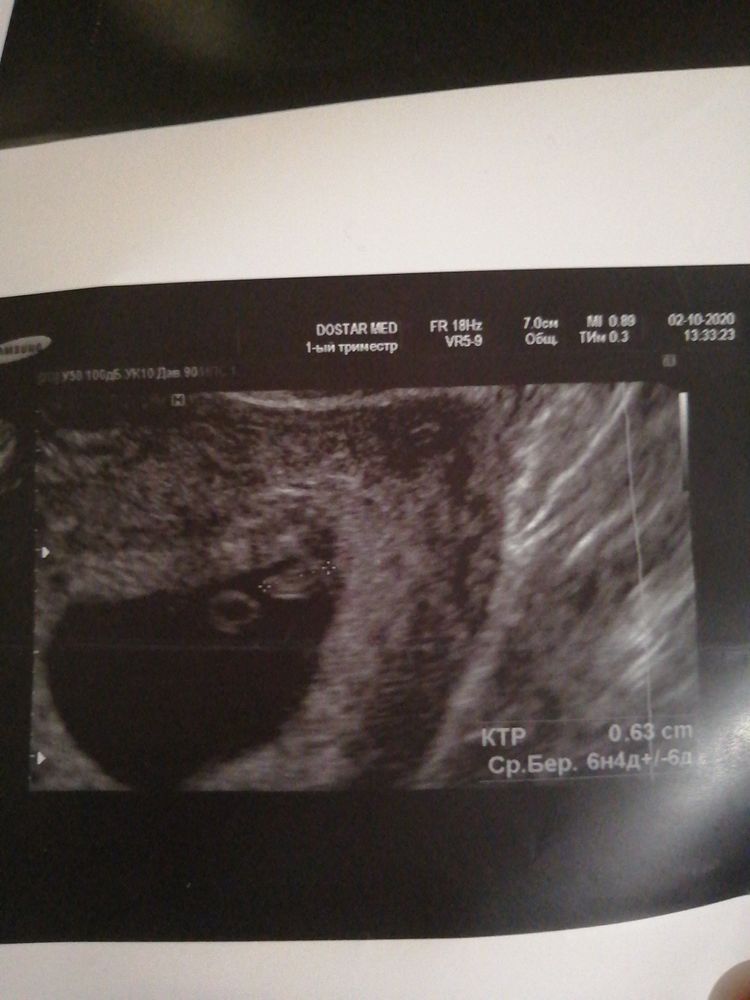

НЮША (ник в ИГ Visla79), А по рамзи можете посмотреть🙏

НЮША (ник в ИГ Visla79), узи вагинальное срок 6,4недель